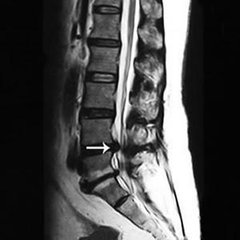

椎管狭窄的危害有什么?随着人的年龄的增长,身体的机能也会出现退化,总是会有这样那样的并会出现,其中像骨病是较为突出的,像腰椎间盘突出、腰椎管狭窄等都会出现。这类骨病危害很大,腰痛、乏力、腰腿麻木、竞争性不行等都是常见的症状。那么,椎管狭窄会有哪些危害呢?下面就和大家介绍一下。 >>>椎管狭窄的症状有哪些你了解吗?

走不动路便是腰椎管狭窄的危害之一,也是较具代表性的症状。腰椎管狭窄多见于中老年,男性居多,多体现为慢性或复发性腰背痛有时伴有坐骨神经痛。腰过伸运动时痛苦加剧。痛苦继续数月致使数年进而出现典型的间歇性跛行。 >>>椎管狭窄的预防要从什么时候开始?如何预防?点击咨询

在久站或行走一段后因为腰椎伸直脊柱前凸,使神经根受压加剧或因神经细胞需氧量增加而呈相对缺氧情况,因而惹起下肢麻痹肌痉挛痛苦和跛行在歇息或折腰后,神经根受压和神经缺氧情况好转痛苦消逝。神经系统体征有下肢肌力削弱,肌肉萎缩,感觉反射反常和大小便功用妨碍。感觉妨碍出现一般迟于运动妨碍。 >>>我的这些症状严重吗?该怎么治疗较好?